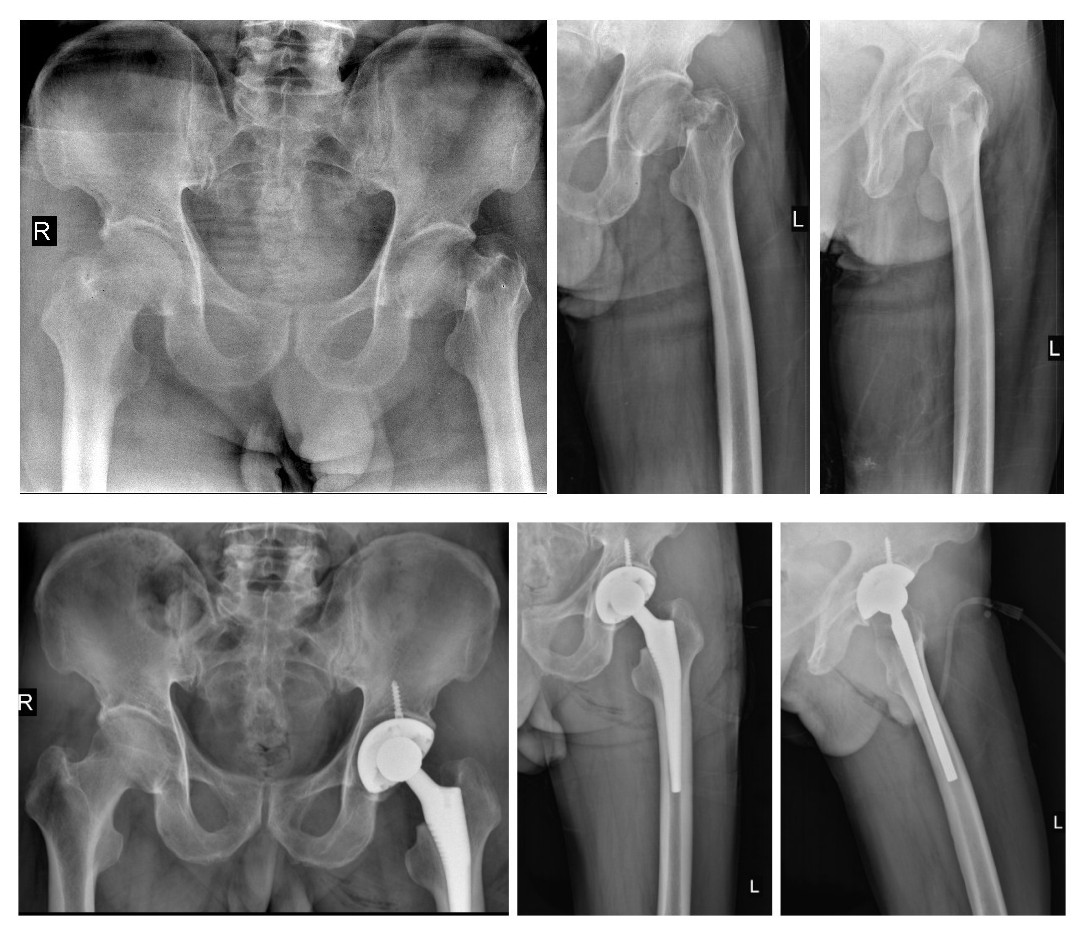

附部分骨折患者术前、术后照片

全髋置换